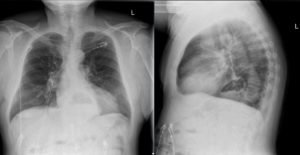

The two-view chest X-ray shows mild opacification of the bilateral lower lobes concerning for pneumonia (red arrows). Incidental retrocardiac opacity with air-fluid level consistent with large hiatal hernia is also observed (green arrow).

In this case, the chest X-ray was concerning for pneumonia, and a large, incidental hiatal hernia was also appreciated. Patient was started on antibiotics for the pneumonia and admitted to internal medicine. The hiatal hernia was not operated on because the patient was asymptomatic.